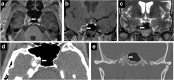

Meckel's cave is a dural recess in the posteromedial portion of the middle cranial fossa that acts as a conduit for the trigeminal nerve between the prepontine cistern and the cavernous sinus, and houses the Gasserian ganglion and proximal rootlets of the trigeminal nerve. It serves as a major pathway in perineural spread of pathologies such as head and neck neoplasms, automatically upstaging tumours, and is a key structure to assess in cases of trigeminal neuralgia. The purpose of this pictorial review is threefold: (1) to review the normal anatomy of Meckel's cave; (2) to describe imaging findings that identify disease involving Meckel's cave; (3) to present case examples of trigeminal and non-trigeminal processes affecting Meckel's cave.

Teaching points: • Meckel's cave contains the trigeminal nerve between prepontine cistern and cavernous sinus. • Assessment is essential for perineural spread of disease and trigeminal neuralgia. • Key imaging: neural enhancement, enlargement, perineural fat/CSF effacement, skull base foraminal changes.